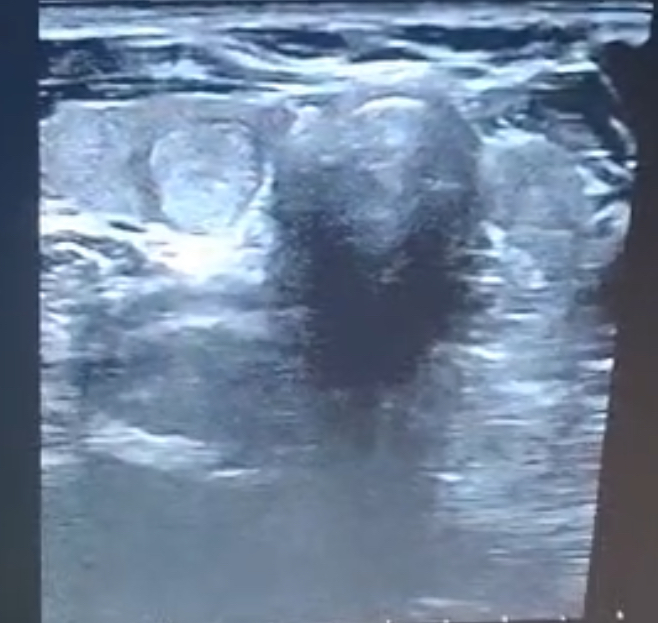

Hallazgos ecográficos

Al disponer de ecógrafo en el centro de salud se decide realizar ecografía de cuello para valoración según la clasificación de Sistema de Informes y datos de imágenes tiroideas (TI-RADS) con respecto a criterios ecográficos de malignidad. Además se revisan analíticas y nunca ha presentado alteración de hormonas tiroideas.

En la ecografía realizada se diagnostica un nódulo tiroideo en lóbulo derecho de mayores dimensiones anteroposteriores que longitudinales. Presenta una medida de 9,3 milímetros en anteroposterior. Además de presentar vascularización periférica.

Al realizar la categorización por los criterios TI-RADS: presenta 4 puntos que es moderadamente riesgo de malignidad.